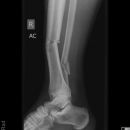

Sprunggelenk

Maisonneuve

Es wurden keine Bilder gefunden.